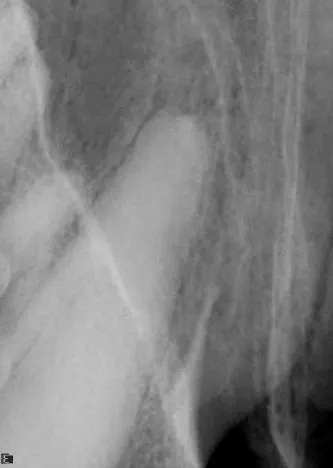

Dental images are best obtained with oral radiography techniques using dental film or a digital sensor and a dental x-ray machine. Locating the dental radiographic unit in the dental operatory makes it quick and easy to take dental radiographs. The film is placed intraorally in most instances to help eliminate overlap of structures. The tube head is manipulated into the correct position for taking the radiograph.

It is less convenient and more technically difficult to obtain high-quality dental images with traditional radiographic techniques. The radiograph machine is usually distant from the dental operatory, making it necessary to move the patient to obtain radiographs. Positioning is more difficult because the tube head is stationary. The need for extraoral film placement increases the difficulty of avoiding overlapping of structures. Dental films placed intraorally can be used with a standard radiographic machine to help with some of these problems; however, the practitioner wishing to incorporate dental radiology into his or her practice is advised to invest in a dedicated dental unit.

Skulls were used for these images. Dental images were obtained with a digital sensor; the traditional radiographs were taken using extraoral technique with a standard radiographic machine.

A dental radiograph showing the roots of a canine tooth, highlighting the surrounding bone structure and periodontal tissues. The image reveals details of the root canal system and any potential signs of dental disease or abnormalities.